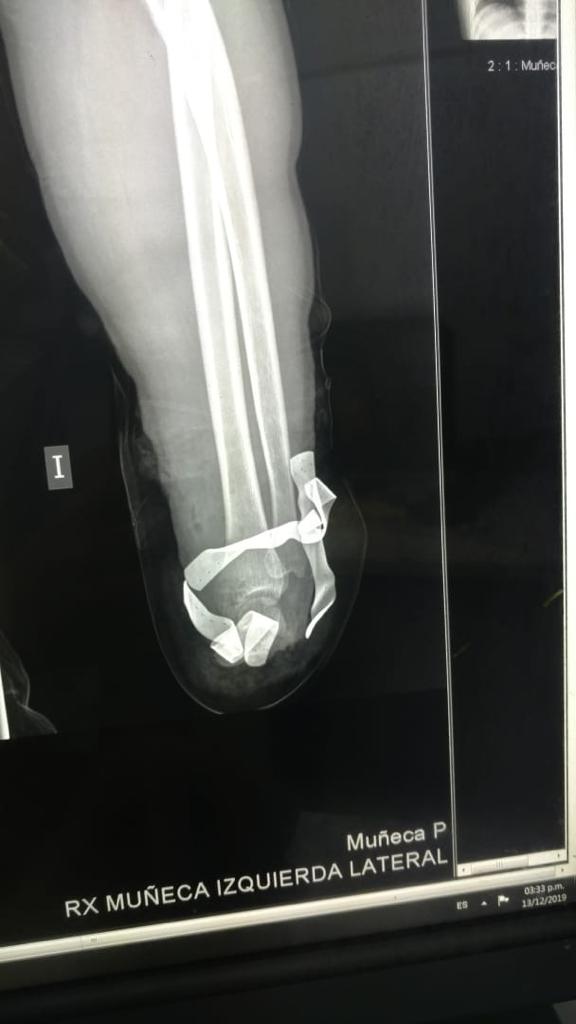

El viernes pasado el paciente sufrió un accidente laboral con derivación de amputación traumática total de la mano izquierda. Acudió a la unidad de urgencias de traumatología del Hospital Central del Instituto de Previsión Social donde se procedió al reimplante de la mano izquierda.